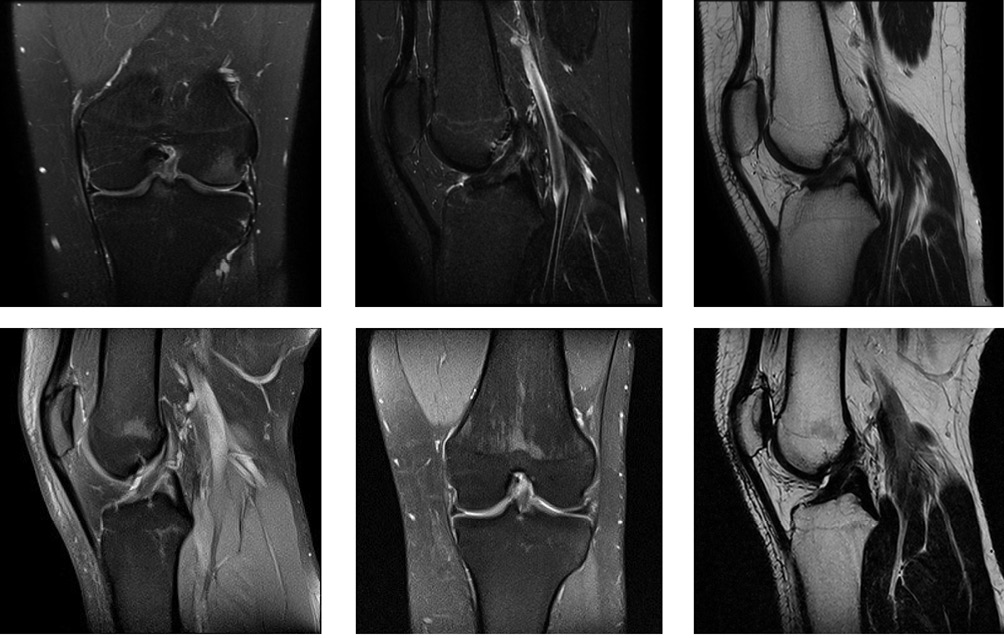

Из анамнеза заболевания известно, что в марте 2025 г. во время одной из тренировок получил травму левого коленного сустава при падении. Учитывая полученную травму, выраженный болевой синдром, амбулаторно по месту жительства была выполнена магнитно-резонансная томография (МРТ) поврежденного сустава: МР-признаки изолированного повреждения ПКС левого коленного сустава (рис. 2А).

Контрольный осмотр через 6 месяцев после травмы: пациент ходит самостоятельно, уверенно, без хромоты. Отек области левого коленного сустава отсутствует, надколенник по средней линии. Симптом баллотирования отрицательный, тесты Лахмана и ПВЯ отрицательные, симметричные с обеих сторон. Субъективных и объективных признаков нестабильности коленного сустава не определяется, ВАШ — 0 баллов. По данным проведенной контрольной МРТ: восстановление структуры передней крестообразной связки (рис. 2Б).

Снимок предоставлен авторами

Рис. 2. Магнитно-резонансная томография левого коленного сустава: А — после травмы; Б — после лечения